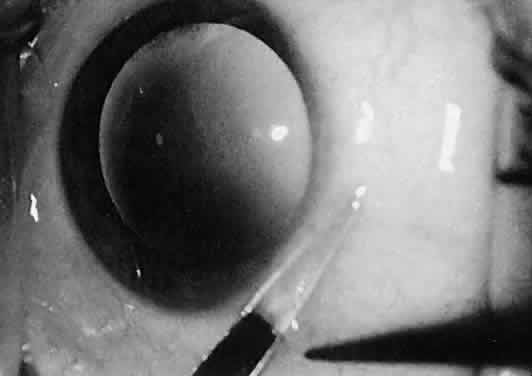

this problem. Scissors also may be used surgically by opening the blades. This maneuver

is employed primarily during blunt dissection (Fig. 26). In this procedure, the surgeon is cutting with the blade tips. Sharp

points can force their way through tissue, whereas blunt tips act as

a spatula and do not damage surrounding structures. When the surgeon dissects

a conjunctival flap or into the sub-Tenon's space, blunt

dissection is preferred. In addition, should the surgeon need to avoid

disturbing the flaps (or a buttonhole), such as a conjunctival flap for

a glaucoma procedure, the surgeon should not use scissors with sharp

tips for blunt dissection. However, when the surgeon is working in an

area that is scarred as a result of previous surgery, the use of sharp

tips may be necessary.  Fig. 26. The sharp points of scissors are forcing their way through the subconjunctival

space. Opening the scissors will result in blunt dissection of

the subconjunctival space. Fig. 26. The sharp points of scissors are forcing their way through the subconjunctival

space. Opening the scissors will result in blunt dissection of

the subconjunctival space.